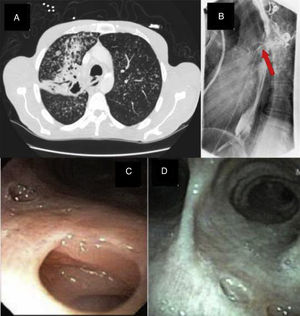

A 46-year-old male, HIV seronegative, smoker, with non-insulin dependent diabetes mellitus presented with complaints of cough, weight loss and dysphagia of six months’ duration. Chest X-ray, followed by CT scans (Fig. 1A) revealed a right upper lobe cavity with a fistulous communication between the trachea and esophagus. Sputum stains were positive for acid fast bacilli consistent with Mycobacterium tuberculosis and the patient was started on antituberculous treatment. A barium esophagogram revealed the presence of a fistulous tract from the esophagus (Fig. 1B), following which an endoscopic gastroduodenoscopy showed a 2.5cm defect in the upper esophagus with a visible fistulous track. Bronchoscopy demonstrated the fistulous tract at the distal right posterior trachea (Fig. 1C). He was managed conservatively with percutaneous gastrostomy feeding and discharged on direct observed therapy for tuberculosis with Rifampicin, isoniazid, pyrazinamide, ethambutol and vitamin B6. After 6 months of treatment, his dysphagia resolved. A repeat barium esophagogram and bronchoscopy (Fig. 1D) showed interval healing of the tracheoesophageal fistula.